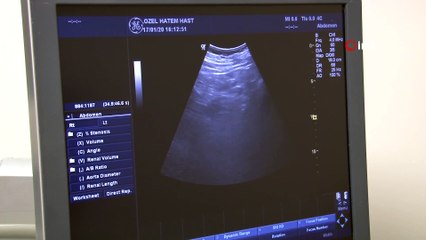

Fazla kilo başa bela... Çünkü fazla kilolar aynı zamanda sağlık sorunlarına kapı aralıyor. Kiloya bağlı hastalıkların başında kalp-damar rahatsızlıkları geliyor. diyabet, migren, uyku apnesi gibi daha bir dizi hastalığın nedenleri arasında da yine fazla kilolar önemli bir yer tutuyor.